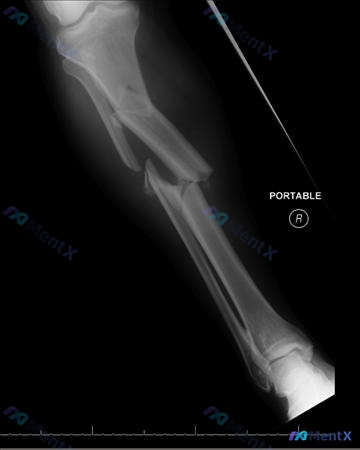

整理了一个很有教学意义的创伤骨科病例,核心是髓内钉固定中阻挡螺钉(Poller/Blocking Screw)的空间力学应用。 --- 病例概况 - 患者:75岁男性 - 受伤机制:过马路时被车撞伤 - 主诉:右腿疼痛 - 查体:无开放性骨折征象 --- 关键影像表现 看了提供的右小腿正侧位X光片(...